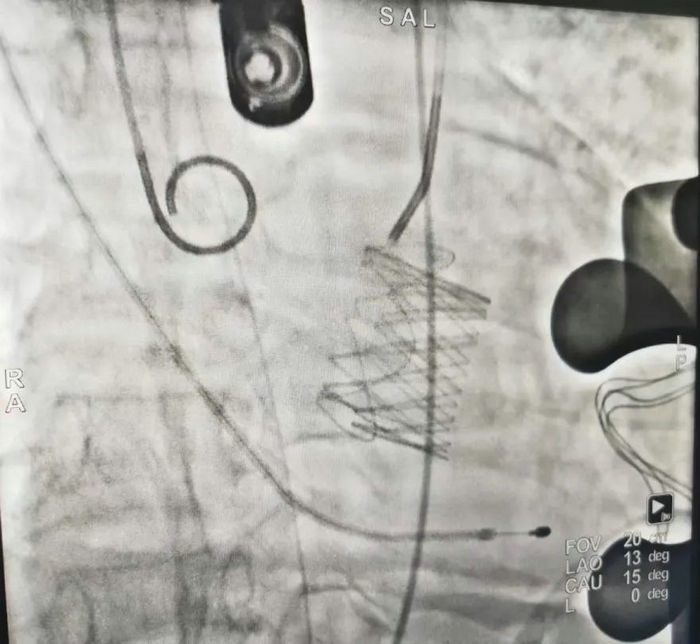

术中精准定位,准备释放前瓣膜形态

瓣膜完美释放,主动脉瓣返流消失

薛亦白副主任介绍道,心尖途径经导管主动脉瓣置换术是一种微创瓣膜置换术,它是股动脉途径经导管主动脉瓣置换术的一个补充,无需开胸、无需体外循环、手术创伤小,通过将可压缩的人工生物瓣膜加工后装载入一个特殊设计的输送系统,在杂交手术间X线引导微创下通过心尖途径将人工瓣膜输送到主动脉瓣,选取合适的位置释放,从而完成人工瓣膜植入,恢复正常的瓣膜功能。

经过充分的评估及积极的术前准备,2023年11月21日,在医院麻醉科、导管室和手术室等医护团队的默契配合下,高兴才主任、薛亦白副主任带领手术团队通过患者胸壁单切口穿刺心尖,精准操作将人工瓣膜在指定位置释放。术中复查食道超声提示瓣膜无返流,跨瓣压差恢复正常,心脏恢复正常功能。术后1小时老人顺利清醒,术后10小时顺利脱离呼吸机,术后第2天老人家便可简单下地活动,术后7天,经过心胸外科医护团队的精心指导及护理,老人家开开心心的康复出院了,住院周期相较常规开胸手术大大缩短。